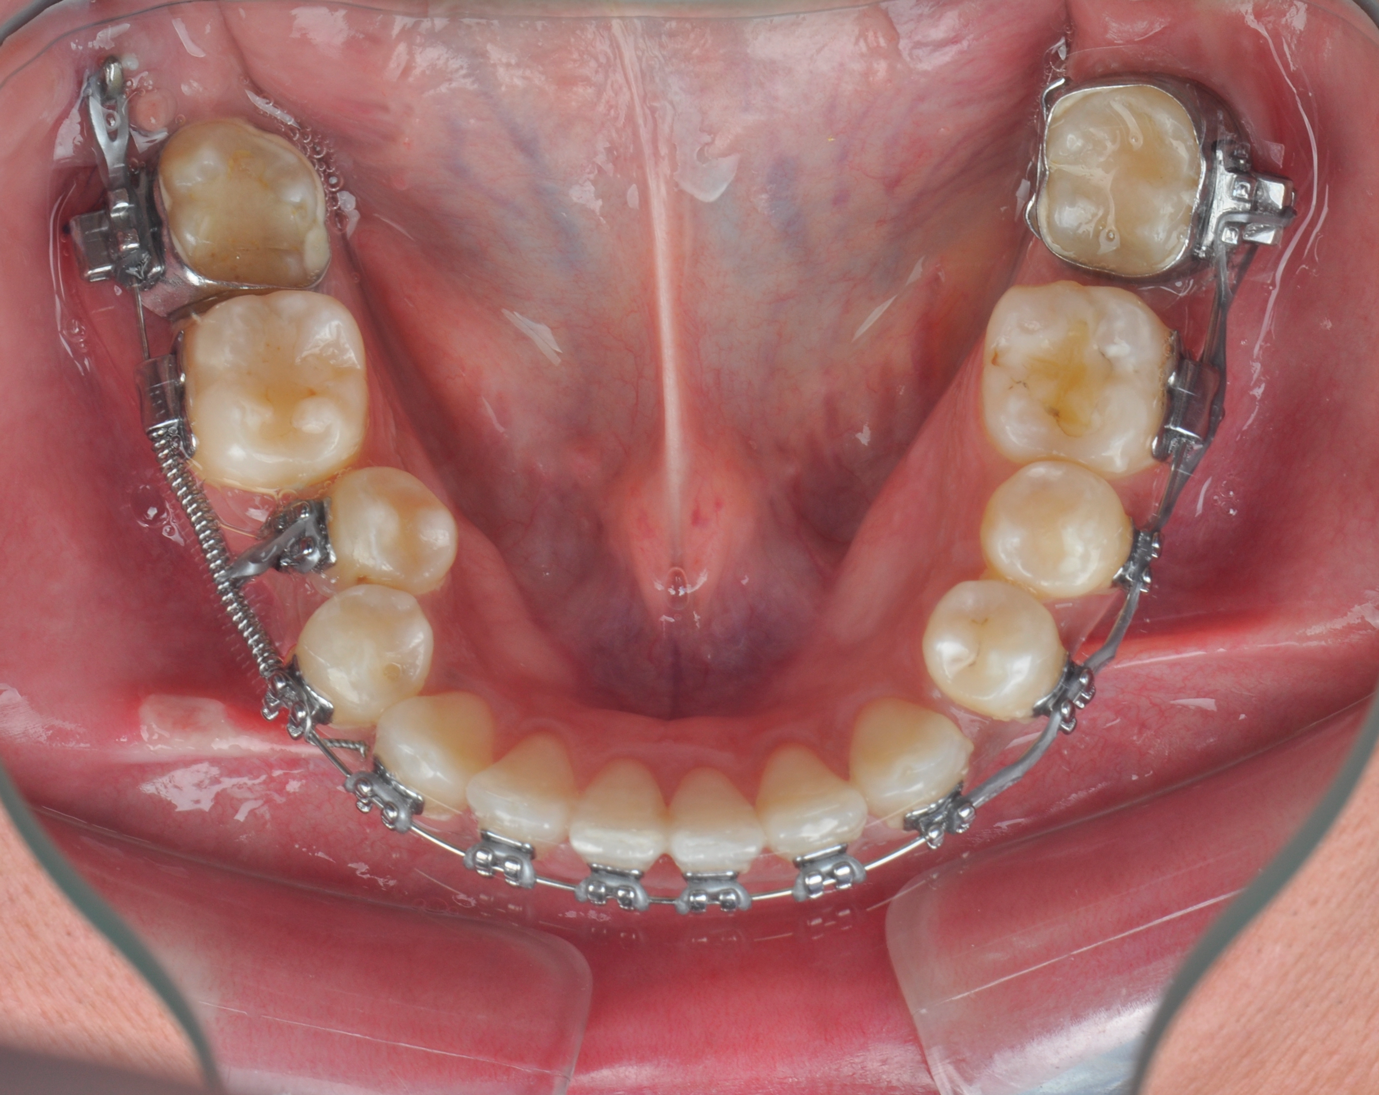

Fig 4. Miniplate in the lower posterior used to perform alignment of a very crowded lower arch during preparatory orthodontics for a class III adult female patient requiring double jaw surgery. Fig 4: Crowding present before presurgical orthodontics. Fig 5: Crowding corrected using the miniplate as anchorage.

Figure 4

Fig 5. Miniplate in the lower posterior used to perform alignment of a very crowded lower arch during preparatory orthodontics for a class III adult female patient requiring double jaw surgery. Fig 4: Crowding present before presurgical orthodontics. Fig 5: Crowding corrected using the miniplate as anchorage.

Figure 5